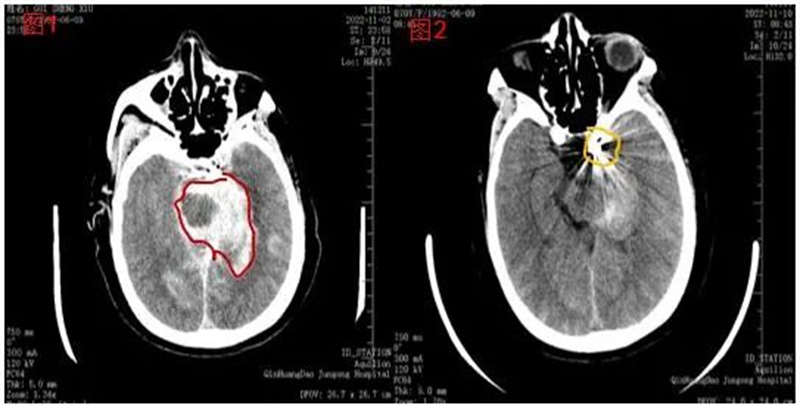

头颅CT图像:

(图1)术后即刻:可见造影剂渗出及出血(红圈内白色阴影)

(图2)术后8天:造影剂吸收完毕,出血量较前明显减少(黄圈内呈像钻石一样闪耀的是栓塞动脉瘤的弹簧圈)